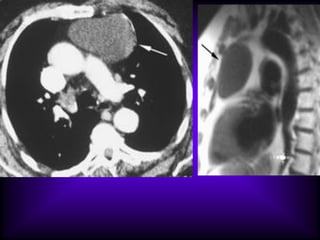

Mediastinal Cysts

The CT features of benign

mediastinal cyst are

(a) a smooth, oval or tubular mass with a well-

defined thin wall that usually enhances after

intravascular administration of contrast

material,

(b) homogeneous attenuation, usually in the

range of water attenuation (0–20 HU),

(c) no enhancement of cyst contents, and

(d) no infiltration of adjacent mediastinal

structures.

Cysts that contain serous fluid typically have

long T1 and T2 relaxation values, which

produce low signal intensity on T1-weighted

MR images and high signal intensity on T2-

weighted images.

Because cysts containing nonserous

fluid can have high attenuation at CT,

they may be mistaken for solid

lesions. MR imaging can be useful in

showing the cystic nature of these

masses because these cysts continue

to have characteristically high signal

intensity when imaged with T2-

weighted sequences regardless of the

nature of the cyst contents